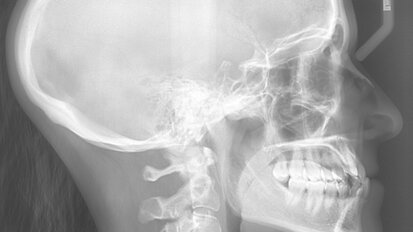

Hybridní terapie alignery